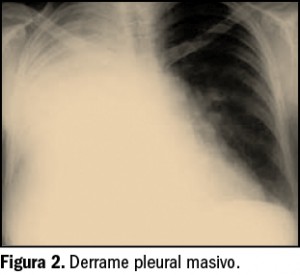

No obstante, algunos expertos apuntan a que la listeriosis es una enfermedad emergente que, por el momento, se considera infradiagnosticada y con importantes lagunas a nivel epidemiológico. Así, un reciente estudio epidemiológico ha analizado los datos –limitados en calidad y cantidad– de hospitalizaciones por listeriosis en España entre 1997 y 2015 (Herrador et al., 2019). En ese periodo, según la base de datos de altas hospitalarias centralizada del Ministerio de Sanidad (Conjunto Mínimo Básico de Datos), se tiene constancia de 5.696 hospitalizaciones con diagnóstico de listeriosis (edad media de los pacientes 58,6 años, 59% hombres). La tasa media fue de 0,67 casos por 100.000 habitantes, con una tendencia creciente en el número de hospitalizaciones durante el período de estudio y con las mayores tasas correspondientes al grupo etario de >65 años, seguido por el grupo de 45 a 64 años (Figura 2).